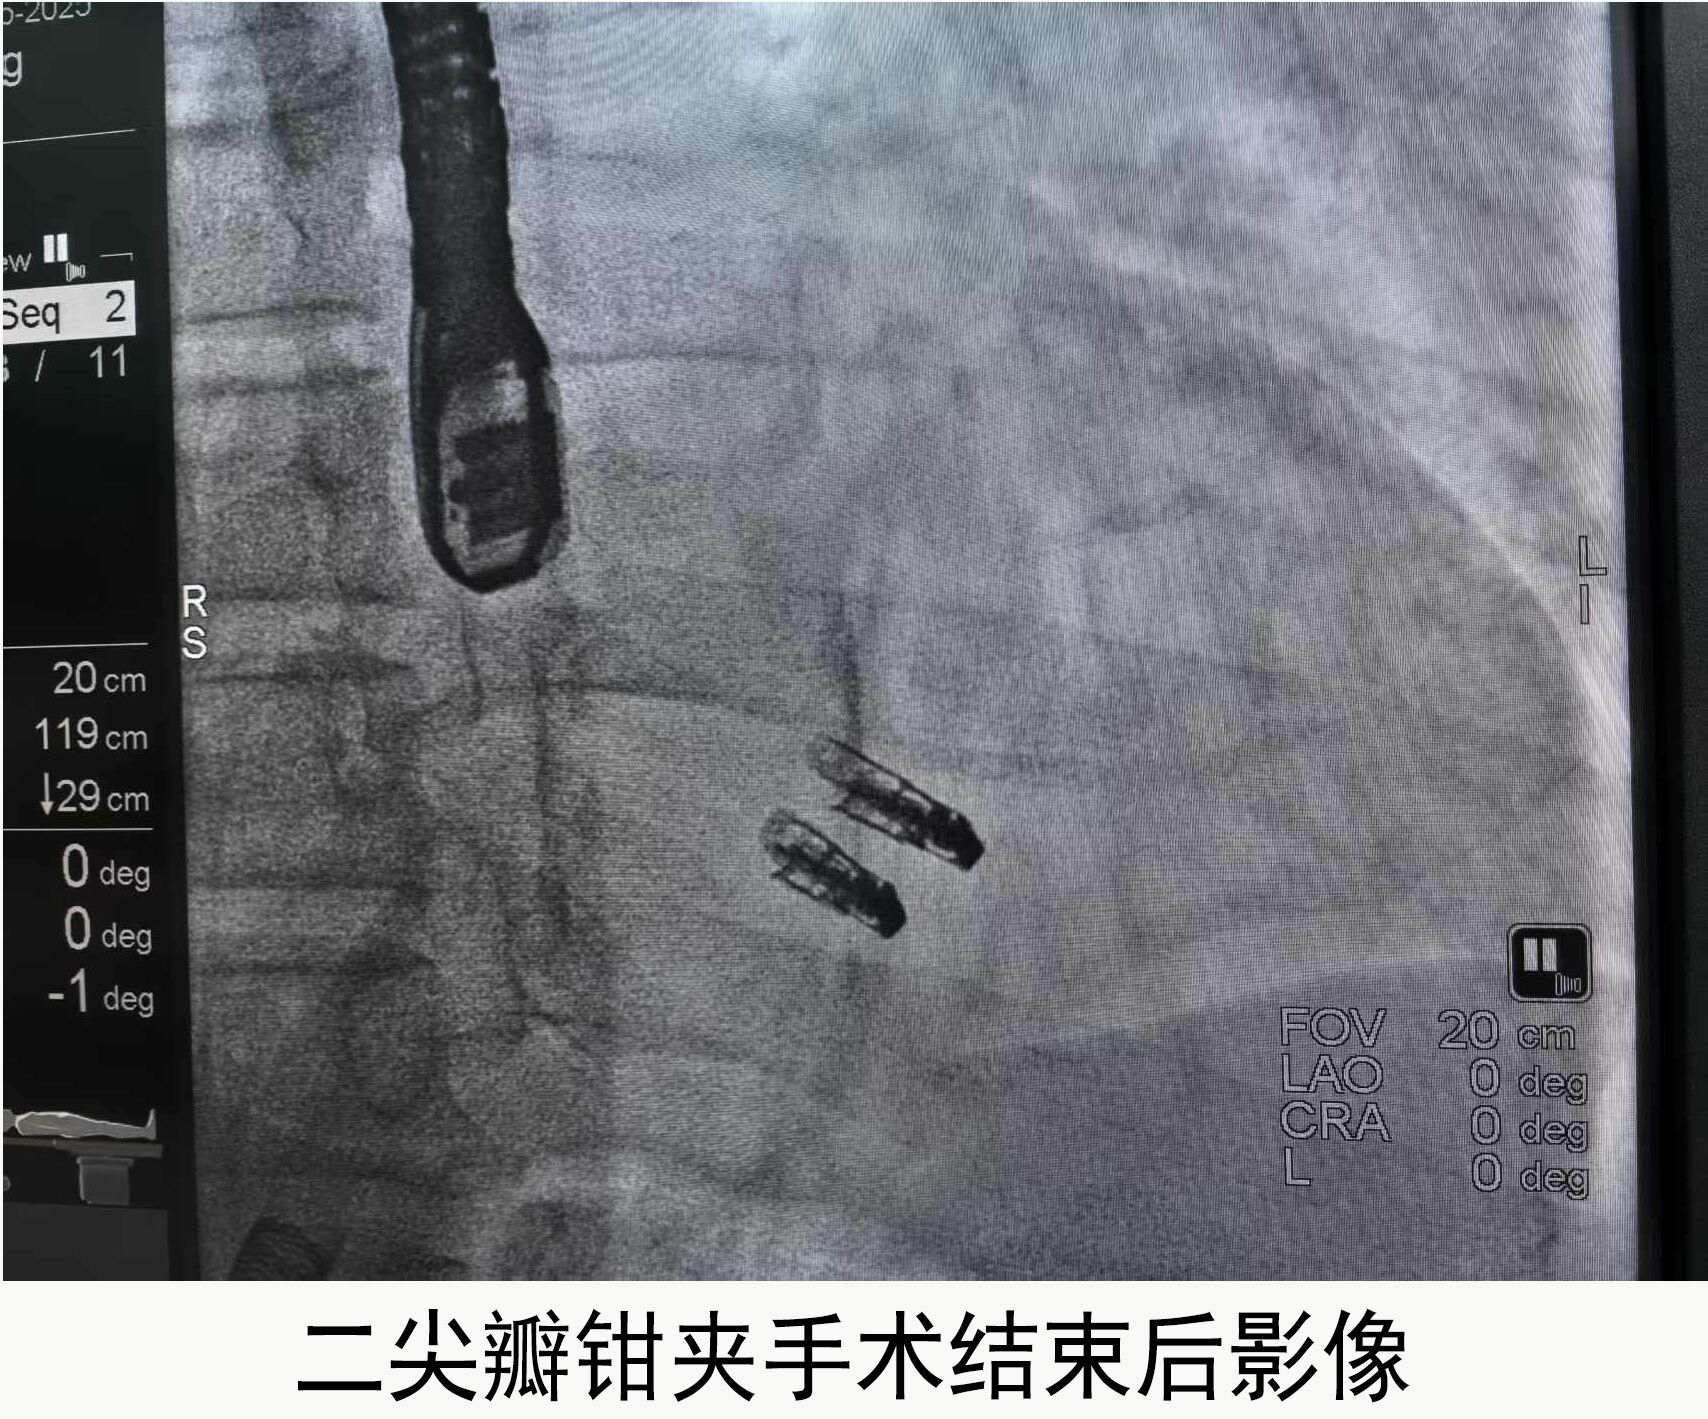

手术方案征得患者及家属同意后,2月17日13:30手术正式开始。在心内科学科带头人袁伟教授带领下,超声医学科、麻醉科、DSA导管室团队等多科室通力合作,实施手术。术中经食道三维超声引导,团队从患者大腿根部的右侧股静脉入路,经房间隔穿刺后插入可操控导引导管,从导管中送入特制的二尖瓣钳夹器,到达二尖瓣关闭不全的部位后,打开夹子,把二尖瓣的两个瓣叶夹在一起。这样,原本关闭不严的二尖瓣就可以恢复完全闭合状态。

术后复查彩超二尖瓣返流消失,心脏杂音消失。术后第二天,赵先生已下床活动,无明显胸闷气喘等不适症状。

戴芝银主任介绍,二尖瓣钳夹术作为结构性心脏病介入领域的前沿新技术,无需开刀,创伤小、恢复快,患者接受度高,是未来心脏瓣膜疾病治疗所趋。“本次手术的顺利开展,标志着江大附院心内科团队在结构性心脏病微创介入治疗领域的又一次重大突破。”